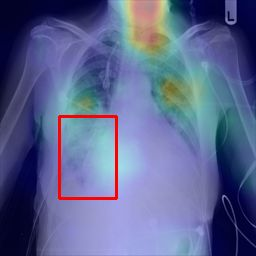

Deployments of artificial intelligence in medical diagnostics mandate not just accuracy and efficacy but also trust, emphasizing the need for explainability in machine decisions. The recent trend in automated medical image diagnostics leans towards the deployment of Transformer-based architectures, credited to their impressive capabilities. Since the self-attention feature of transformers contributes towards identifying crucial regions during the classification process, they enhance the trustability of the methods. However, the complex intricacies of these attention mechanisms may fall short of effectively pinpointing the regions of interest directly influencing AI decisions. Our research endeavors to innovate a unique attention block that underscores the correlation between 'regions' rather than 'pixels'. To address this challenge, we introduce an innovative system grounded in prototype learning, featuring an advanced self-attention mechanism that goes beyond conventional ad-hoc visual explanation techniques by offering comprehensible visual insights. A combined quantitative and qualitative methodological approach was used to demonstrate the effectiveness of the proposed method on the large-scale NIH chest X-ray dataset. Experimental results showed that our proposed method offers a promising direction for explainability, which can lead to the development of more trustable systems, which can facilitate easier and rapid adoption of such technology into routine clinics. The code is available at www.github.com/NUBagcilab/r2r_proto.